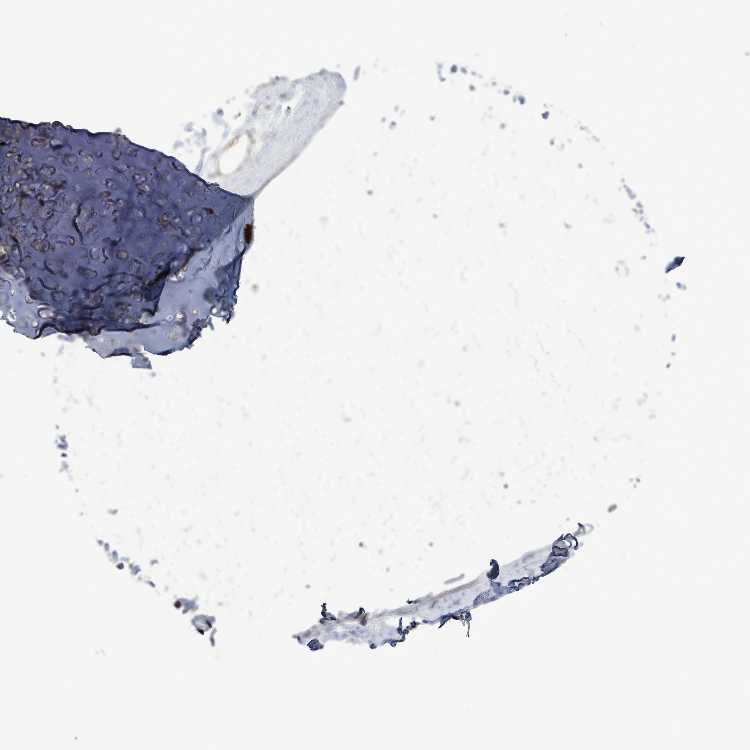

SOFT TISSUE 1 - Antibody stainingi

Antibody staining in the annotated cell types in the current human tissue is reported as not detected, low, medium, or high, based on conventional immunohistochemistry profiling in selected tissues. This score is based on the combination of the staining intensity and fraction of stained cells.

Each image is clickable and will lead to virtual microscopy that enables deeper exploration of all samples and also displays staining intensity scores, fraction scores and subcellular localization as well as patient and tissue information for each sample.

Antibody HPA049418

Chondrocytes Low